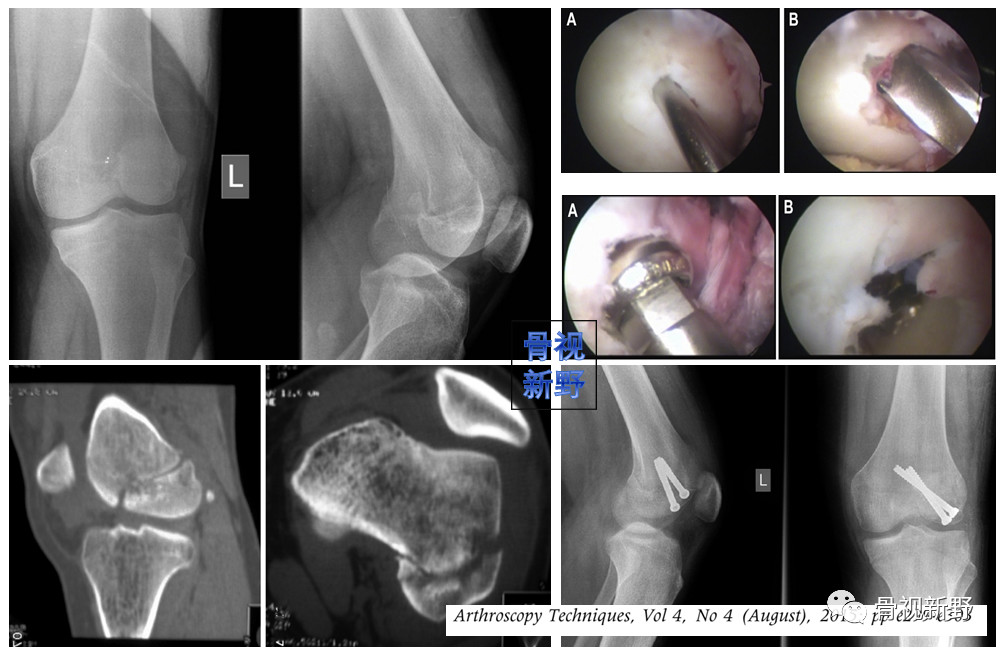

医源性损伤医源性Hoffa骨折见于膝关节ACL重建术。如果骨隧道位置太靠后或较小的股骨放置较粗的韧带,则有导致Hoffa骨折的潜在危险。

影像诊断:部分Hoffa骨折X线片不能提供明确的诊断,漏诊率较高。需要CT或MRI检查,并根据患者的病史、查体及影像学检查予以确诊。

部分Hoffa骨折普通X光片易漏诊

CT扫描在矢状位、轴位容易发现骨折及骨折线的走形方向

关节镜微创入路

关节镜微创手术可减少软组织剥离和出血量,术后关节功能及软组织恢复较好。但目前仅有少数个案报道,尚并无充分证据支持关节镜辅助Hoffa骨折。